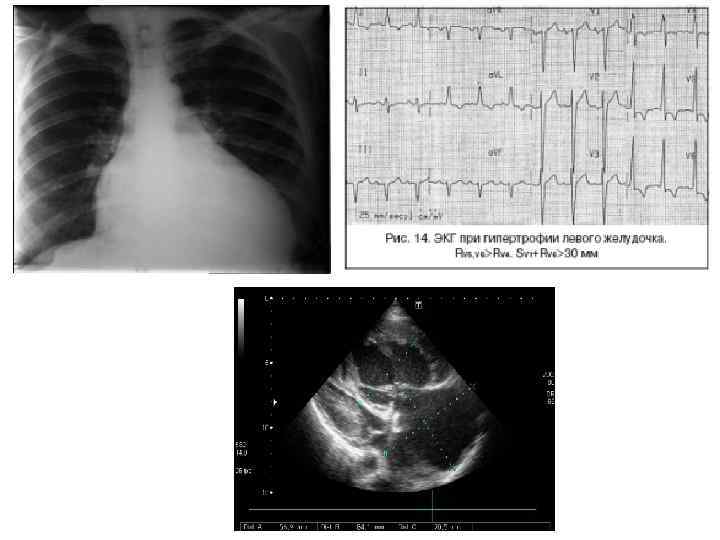

5. Головокружение, головные боли. 6. Слух (звон в ушах, ухудшение слуха). 7. Проблемы в психоэмоциональной сфере (депрессии, тревожные расстройства). 8. Больные жалуются на затруднение дыхания и боли в груди, боли по типу стенокардитических, учащенное сердцебиение. 9. Изменения со стороны желудочно-кишечного тракта характеризуются тошнотой, рвотой, диареей, болями в животе.

На МРТ головного мозга могут присутствовать характерные для болезни Фабри признаки: на Т 2 -изображении может присутствовать гиперинтенсивный сигнал в белом веществе фронтальных и теменных долей. На Т 1 -взвешенном изображении наблюдается высокий сигнал от серого вещества глубинных структур, особенно заднего бугорка таламуса. Изолированное поражение заднего бугорка таламуса считается патогномоничным для болезни Фабри. Также на МР-картине часты сосудистые мальформации, преимущественно представленные долихоэктазиями вертебробазилярной артерии.